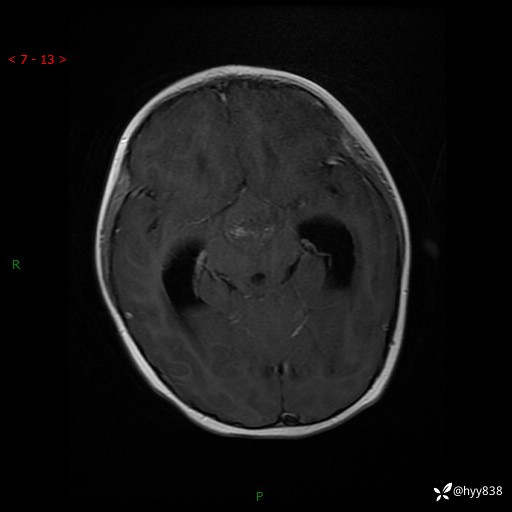

颅脑CT平扫

颅脑MRI平扫+增强